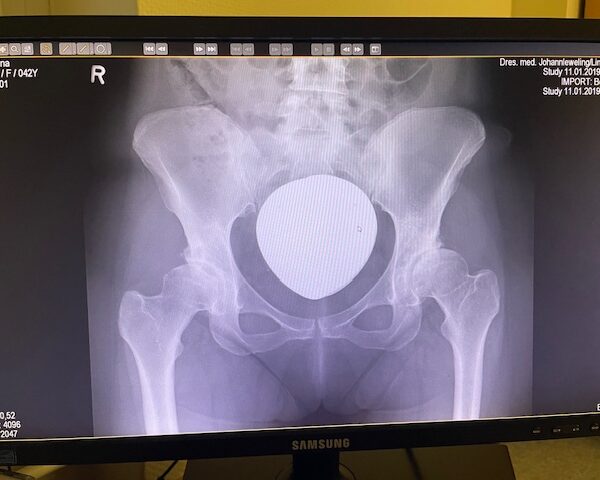

Η ασθενής είχε απευθυνθεί από χρόνια σε πολλούς συναδέλφους ορθοπεδικούς στην Ελλάδα και το εξωτερικό. Είχε προηγηθεί ήδη διεξοδικός απεικονιστικός έλεγχος (ακτινογραφίες λεκάνης και ισχίου, αξονική και μαγνητική τομογραφία).

Το 2024 όταν πλέον η ασθενής απευθύνθηκε σε εμένα, ακολούθησε εκ νέου ακτινογραφικός έλεγχος ώστε να μπορέσει να πραγματοποιηθεί ο προεγχειρητικός ψηφιακός σχεδιασμός του Χειρουργείου.

Ο ακτινογραφικός έλεγχος έδειχνε προχωρημένες εκφυλιστικές αλλοιώσεις και αλλοίωση της ανατομίας της κοτύλης και του μηριαίου.